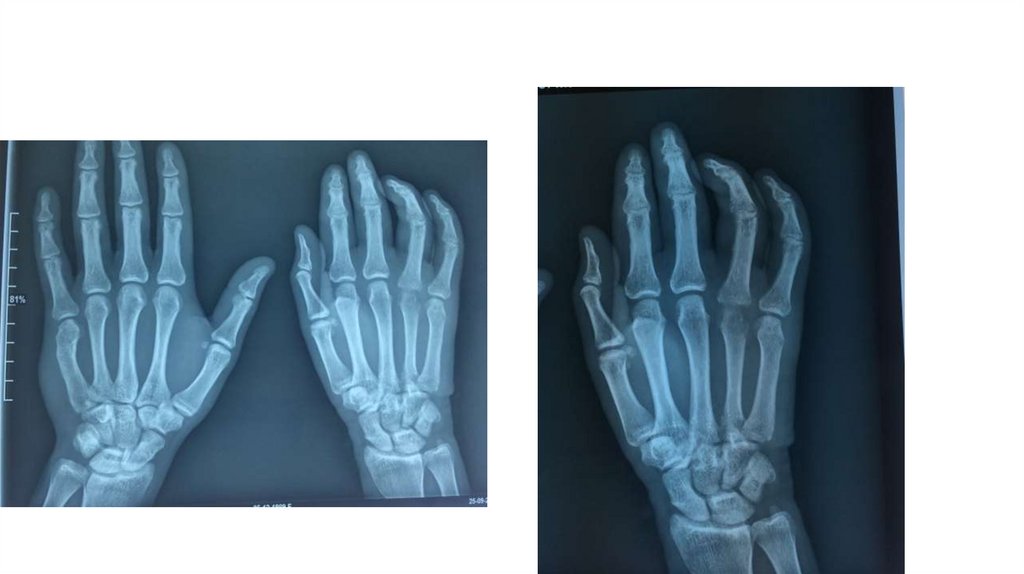

Воспалительные заболевания опорнодвигательного аппарата

«Воспалительные

заболевания опорнодвигательного аппарата»